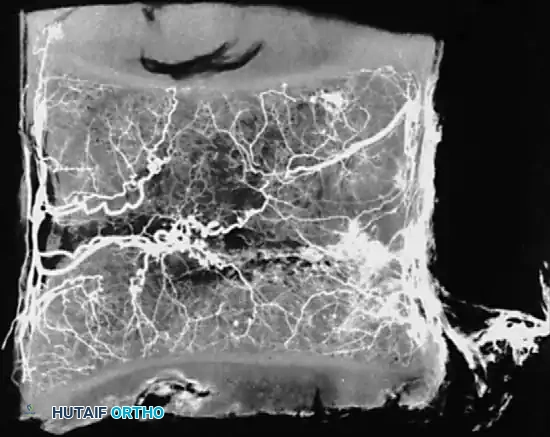

Whalen et al. investigated the microvasculature of the vertebral endplates, describing vessels oriented obliquely within the cartilage, directing toward the intervertebral disc. These vessels originate from circumferential vessels fed by the arterial plexus outside the perichondrium or from adjacent metaphyseal marrow vessels.

A

Crucially, Whalen's team concluded that the intervertebral disc is avascular even in infants, whereas the surrounding cartilaginous material is highly vascular. The cartilaginous endplate represents the anatomical terminus of the arterial supply, regardless of the patient's age.

In 1976, Crock and Yoshizawa mapped the venous microcirculation of the vertebral endplate. The venous system begins exactly where the arterial circulation ends. Large subvenous channels run horizontally and parallel to the endplate. This horizontal system drains through small vertical veins that perforate the endplate, connecting with horizontal vessels in the adjacent cancellous bone.